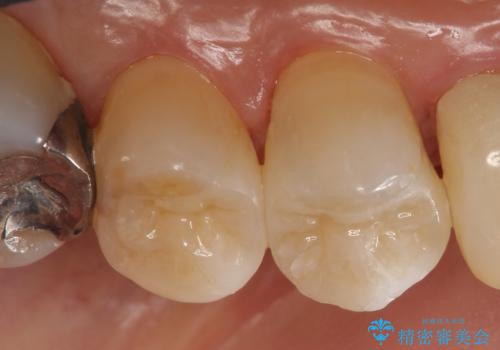

- 左上5番目の歯の銀歯が外れてしまったため、セラミックインレーによる修復を行った症例です。

手前の左上4番目の歯も虫歯だったため、セラミックインレーによる修復を行いました。

当院のセラミックインレーはemaxという強度と審美性に優れた材料を使用しています。

またプレス方式でインレーを製作しているため、削り出しで製作するCADCAMより優れた適合性も持ち合わせており、虫歯が再発しにくい修復物です。